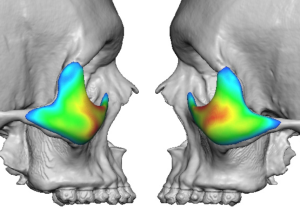

3D CT Findings in NOV

- Fully customized based on CT anatomy

- Accounts for asymmetry, rim depth, and globe position

Vector Correction Strategy

Rather than simply adding volume, the implant is designed to reposition skeletal support:

- Converts a negative vector to neutral or slightly positive

- Advances the infraorbital support structure to match or exceed globe projection